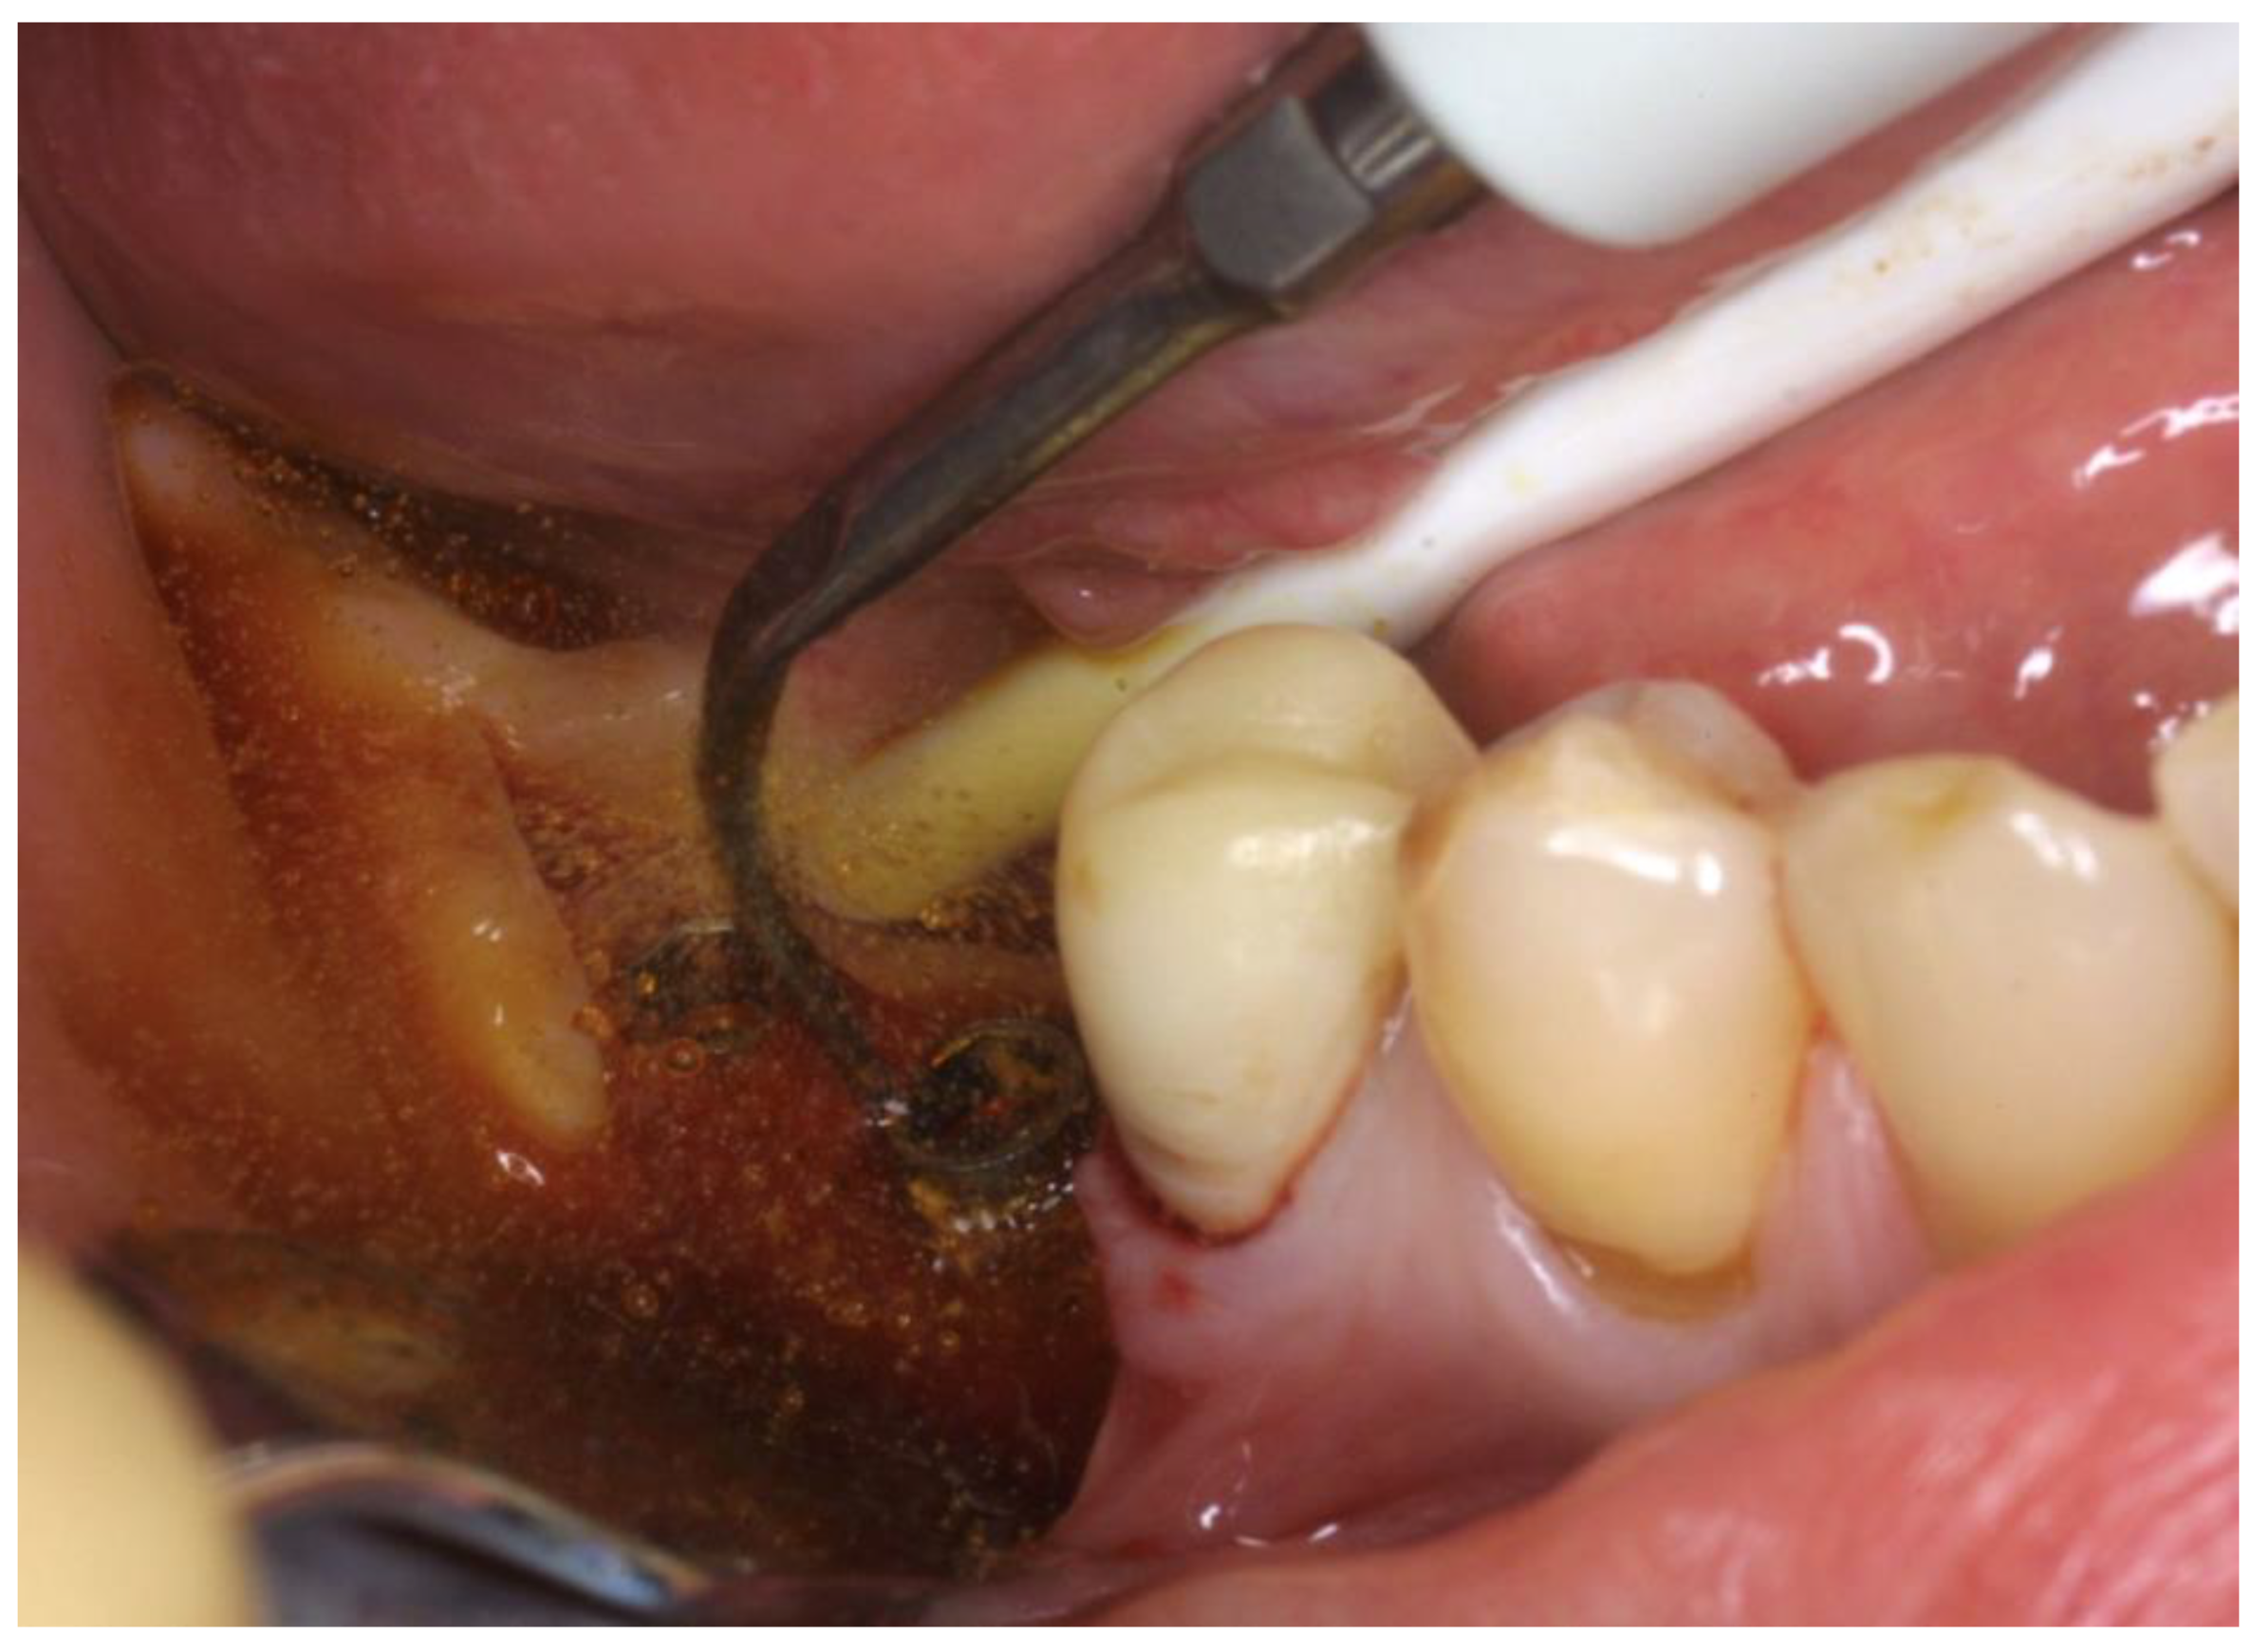

Figure 3.

Ultrasonic instrumentation with water–Betadine irrigation (5:1 ratio).